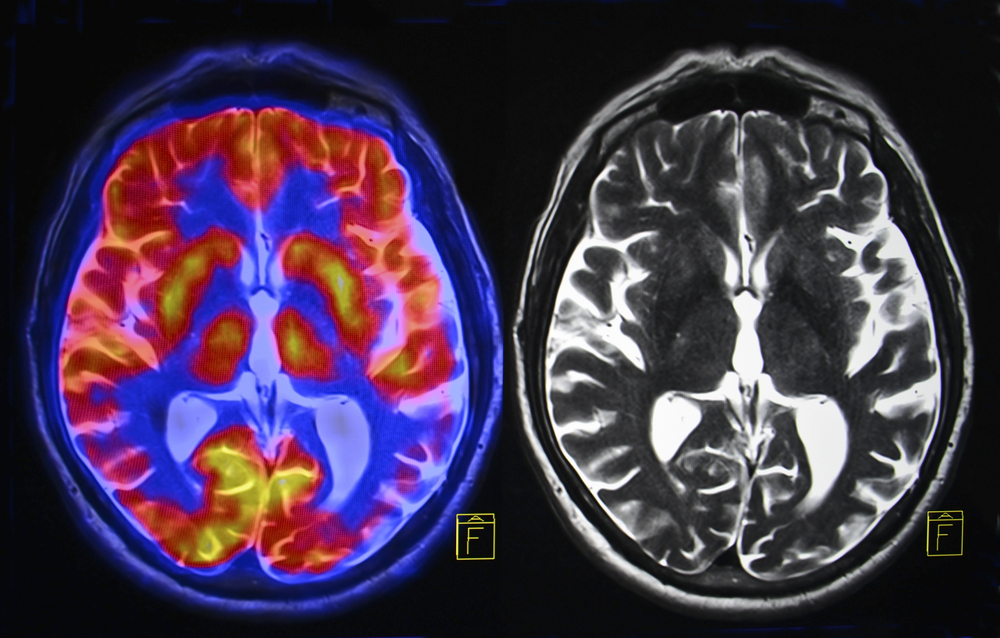

To understand the diagnosis, one must look at the tool behind the terrifying images. The technology used is called single-photon emission tomography, or SPECT. It involves injecting radioactive chemicals into the bloodstream to track how blood flows through the brain. The resulting 3D images are colorful and visually striking, which makes them incredibly persuasive. When a specialist points to a dark patch on a monitor and calls it a “hole,” it looks like undeniable proof of damage.

However, scientific experts warn that these images can be misleading. Sarah Hellewell, a research fellow at Curtin University, explains that what appears to be a hole is simply an area of reduced blood flow. It is not a physical gap in the brain tissue. While SPECT has legitimate uses for specific heart or bone conditions, the broader scientific community remains highly skeptical of using it to diagnose mental health issues like chronic stress, ADHD, or relationship problems.

Experts point out that blood flow fluctuates naturally. It changes based on the time of day, how much sleep a person got, or even simple caffeine intake. Labeling these normal variations as “holes” caused by stress is scientifically unfounded. Critics argue that without credible evidence, these expensive scans risk becoming modern “snake oil,” selling fear rather than medical truth. It is essential to distinguish between a flashy visual and a proven medical reality.